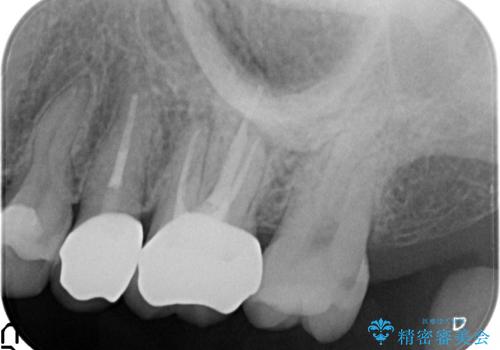

痛みの消失を確認後、オールセラミッククラウンによる補綴を行いました。

今回用いたオールセラミッククラウンはジルコニアフレームという白い素材の上にセラミックを盛っているため、審美性が非常に高いのが特徴です。

また、ジルコニアは人工ダイヤモンドの材料にも使われているほど高い強度を持っており、そのためオールセラミッククラウンは審美性だけでなく、奥歯やブリッジの補綴も可能とするクラウンです。